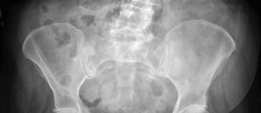

Preoperative digital templating is a mandatory step in the surgical workflow for arthroplasty. Templating was performed on the AP pelvis radiograph, utilizing the contralateral, uninjured hip as a reference for restoring the center of rotation, femoral offset, and leg length. The templating process involves:

Given the patient's age and the presence of proximal femoral osteopenia (Dorr Type B/C bone morphology), templating was directed toward a hybrid total hip arthroplasty construct. This involves an uncemented, press-fit acetabular component and a cemented femoral stem. The templating confirmed that a standard offset cemented stem would adequately restore the patient's native biomechanics.

Acetabular Preparation and Component Implantation

Exposure of the acetabulum was achieved by placing a superior pin in the ilium, an anterior retractor over the anterior wall, and an inferior retractor clearing the transverse acetabular ligament. The labrum and any obstructing osteophytes were excised to fully visualize the true acetabular floor and the teardrop.

Sequential reaming of the acetabulum was performed, starting with a small reamer and increasing in 1mm increments. Reaming was directed medially to the true floor, then expanded peripherally to achieve a bleeding subchondral bone bed. The goal is to achieve a hemispherical construct that allows for a 1-2mm press-fit of the uncemented cup.

Once the appropriate size was reached, a highly porous, titanium-coated hemispherical cup was impacted into place. The target orientation was 40-45 degrees of inclination and 15-20 degrees of anteversion. Excellent primary stability was achieved via the equatorial press-fit. Two cancellous screws were placed in the postero-superior quadrant (the safe zone) to augment initial fixation. A highly cross-linked polyethylene liner was then impacted into the shell.